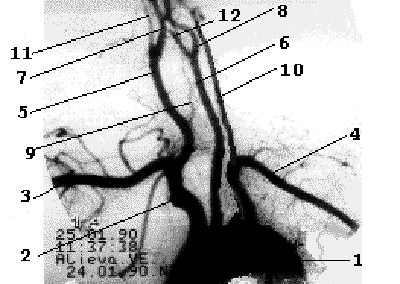

От дуги аорты отходят три основных артериальных ствола - слева общая сонная и подключичная артерии, справа - короткий брахиоцефальный ствол, который делится на правую подключичную и правую общую сонную артерии. Обе позвоночные артерии отходят от соименных подключичных артерий, являясь границей первого и второго сегментов ПКА. Общая сонная артерия у верхнего края щитовидного хряща делится на наружную сонную артерию и внутреннюю сонную артерию (рис. 1.3).

Рис 1.3

Рентгеноанатомия брахиоцефальных ветвей дуги аорты. 1- дуга аорты, 2- брахиоцефальный ствол, 3- правая ПКА, 4- левая ПКА, 5- правая ОСА, 6- левая ОСА, 7- правая ВСА, 8- левая ВСА, 9- правая ПА, 10- левая ПА, 11- правая НСА, 12- левая НСА.